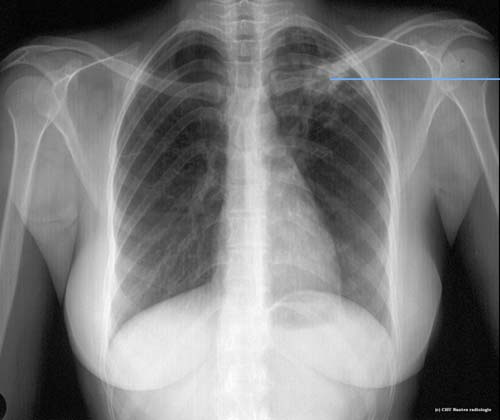

Lésions cavitaires

Opacités à bords flous , mal limitée et à centre clair aérique : caverne d'origine tuberculeuse ( lésion excavée ) du lobe supérieur gauche